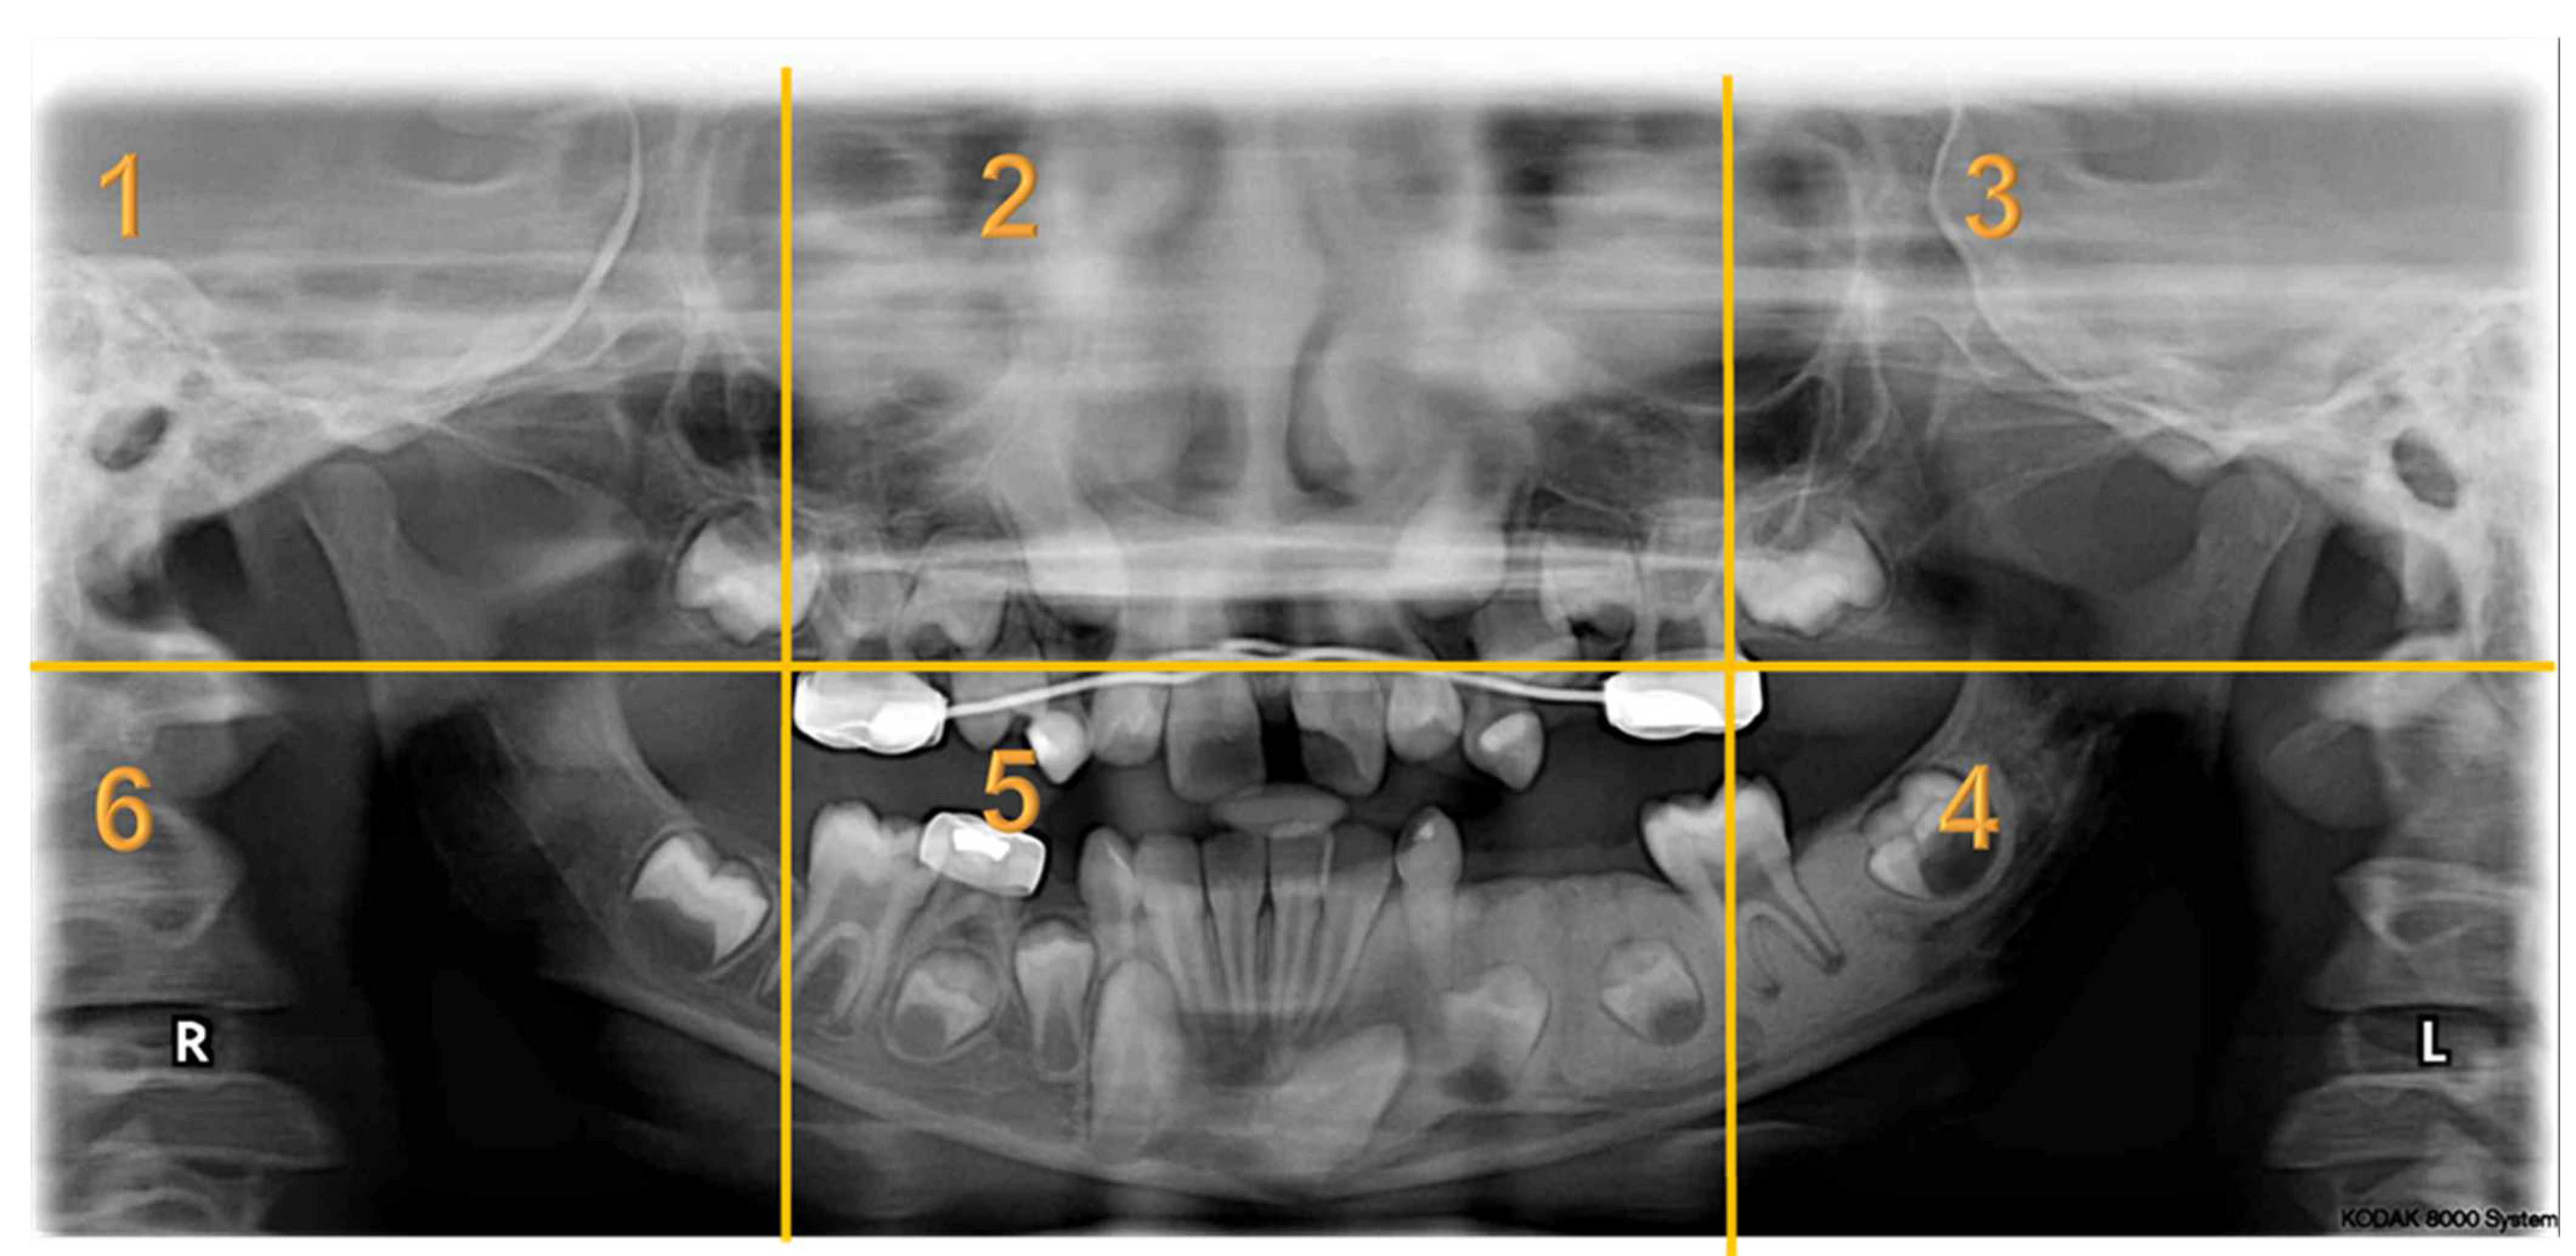

Appendix A. Radiographs Included in the Study

| Radiographs with Abnormalities | Number of Sextants Involved | Number of AOI a | Number of Participants | Total Recorded Observation b |

|---|---|---|---|---|

| Radiograph 1 | Multiple | 3 | 30 | 90 |

| Radiograph 2 | Multiple | 8 | 30 | 240 |

| Radiograph 3 | Single | 2 | 30 | 60 |

| Radiograph 4 | Single | 2 | 30 | 60 |

| Radiograph 5 | Single | 1 | 30 | 30 |

| Radiograph 6 | Single | 1 | 30 | 30 |

| Radiograph 7 | Single | 1 | 30 | 30 |

| Overall Observations | 540 |